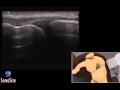

Using 3D animations we have come up with a new way of demonstrating how to perform portable ultrasound examinations. In this educational video you will see a demonstration of the Ultrasound Exam of the Meniscus.

3d of knee 3D How To: Ultrasound Exam of the Meniscus - SonoSite Ultrasound | |